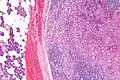

-

-

Intermed. mag.

Intermed. mag. -

Histopathologic features

Basophilic, bland cells similar to acinar cells. Growth pattern: solid - acinar cells, microcytic - small cystic spaces mucinous or eosinophilic, papillary-cystic - large cystic lined by epithelium, follicular - similar to thyroid tissue.

These tumors, which resemble serous acinar cells, vary in their behavior from locally aggressive to blatantly malignant.